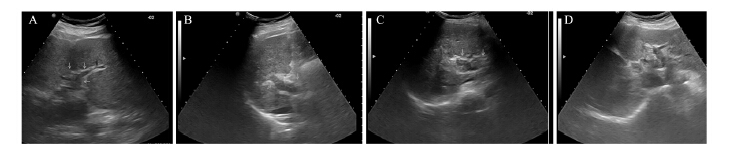

所有患者均按治疗计划顺利完成治疗。通过 超声和增强CT,观察瘤栓的分布范围、大小和 门静脉血流的变化。A组的近期有效率70.59% (24/34),B组的近期有效率67.74%(21/31), 两组疗效比较差异没有统计学意义(χ2=0.062, P=0.804),见表 2、图 2~3。

|

| A: main and right branch of PVTT before HIFU therapy;B:the tumor thrombosis disappeared after HIFU therapy;C: color Doppler rheography after HIFU therapy 图 2 Ⅱ级癌栓高强度聚焦超声治疗前后声像图 Figure 2 Contrast image of grade ⅡPVTT before and after HIFU therapy |